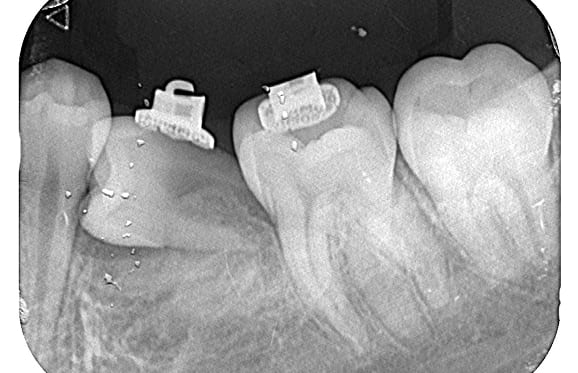

● 先天性の萌出方向異常を部分矯正で治療

藤沢デンタルオフィスの虫歯や破折で先天性の萌出方向異常を部分矯正で治療

01

02

03

04

05

06